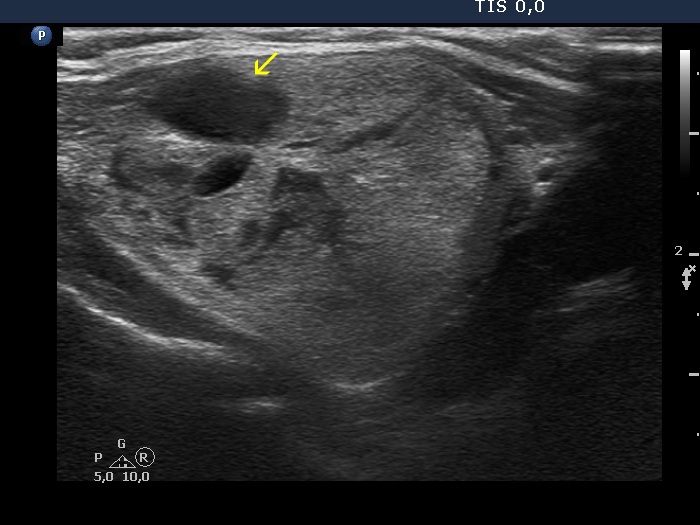

Benign hyperplastic nodules (histology) - case 1633 |

Transverse scan |

Longitudinal scan |

The lobe has multiple nodules, including hypoechoic and iso/hyperechoic lesions, as well. The hypoechoic nodule is brighter than the strap muscle, therefore this is a minimally/moderately hypoechoic lesion.